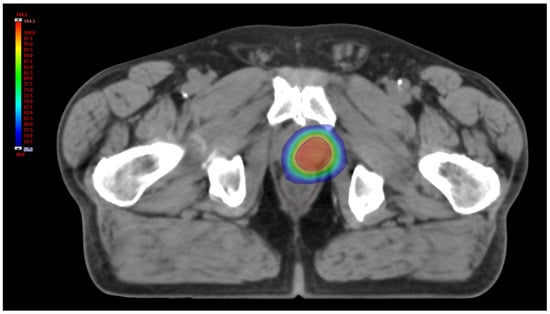

As already extensively described [36], PPR treatment was performed delivering a volumetric modulated arc therapy (VMAT) technique with a course scheme of 35 Gy in seven daily fractions of 5 Gy, five fractions/week (Figure 2); considering an alpha-beta ratio of 1.5 Gy, the total BED at the target was 151.7 Gy [40]. All patients were imaged with a non-contrast-enhanced pre-treatment CT using a 32-slice scanner (Toshiba Aquilion LB, Toshiba Medical Systems Europe, Zoetermeer, the Netherlands). The gross target volume (GTV) was defined with the aid of the (11C)-choline PET as the volume delineated with a semi-automated technique using a fixed threshold of 40% of the maximum signal intensity. To reduce inter-observer variability, minimal manual corrections of the GTV borders were performed to take into account anatomical differences due to possible sub-optimal spatial registration between different image modalities. The dose distributions were calculated on a resolution grid of 2.5 mm or less with Eclipse treatment planning system (TPS) version 13.6, using the Anisotropic Analytical Algorithm version 13.6.23 (Varian Medical System, Palo Alto, CA, USA). For each patient, PET and CT images, together with the dose distributions and GTV contours, were saved in the digital imaging and communications in medicine (DICOM) format. The following analysis, including data conversion, image post processing, feature calculation and model training and validation were performed in Matlab R2021b version: 9.12.0.1927505 R2022a (The MathWorks, Inc., Apple Hill Drive Natick, MA, USA).

Figure 2. Axial view of 3D relative dose distribution (%). Blue line: PTV; brown line: rectum.